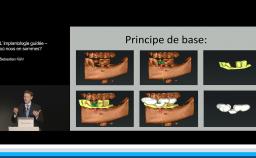

Au cours de cette présentation, le Dr Finelle nous montre tout l’intérêt du digital workflow dans une réhabilitation implantaire en secteur esthétique. Ainsi, à chaque étape de celle-ci, le numérique peut intervenir : au cours du diagnostic, de la chirurgie, de l’empreinte ou encore au cours de la réalisation prothétique.

Au travers de plusieurs cas cliniques, il nous est montré comment différents outils numériques permettent de préparer et d’obtenir une réhabilitation esthétique optimale. Au final, le digital workflow va apporter précision, prédictibilité, facilité de reproduction des formes dans la réhabilitation prothétique implantaire ; c’est également un formidable moyen de communication avec le patient.

- de décrire le workflow numérique du diagnostic à la prothèse définitive